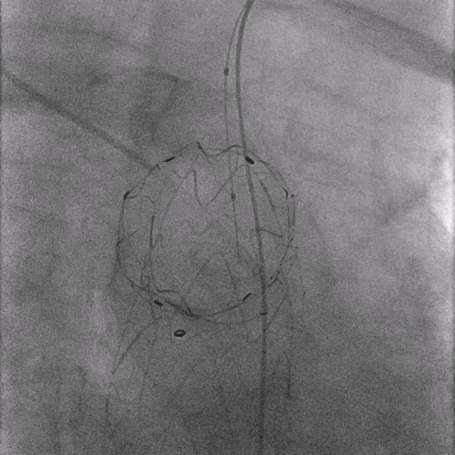

02. 交换0.035"Lunderquist超硬导丝至升主动脉,于左侧颈总动脉开口远端精确定位并释放华脉泰科PTBS3632180覆膜支架。

泥鳅导丝怎么用曲乐丰教授团队:0.018"和0.035"普通泥鳅导丝行胸主动脉弓上分支原位开窗的病例分享_https://www.jmylbn.com_新闻资讯_第28张

植入华脉泰科覆膜支架